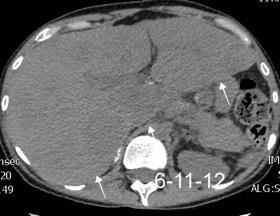

Recibe una puñalada en costado izquierdo

La laceración tiende a ocurrir en la unión

músculotendinosa . (64-90% en el lado izquierdo)

Diafragma “colgante” (“dangling sign”)

TC. Mejor con multicorte. (reconstrucciones).

Asociación: Aire en pared.

Fracturas costal .Rotura esplénica. Neumoperitoneo.

Diafragma discontinúo Herniación de la grasa omental